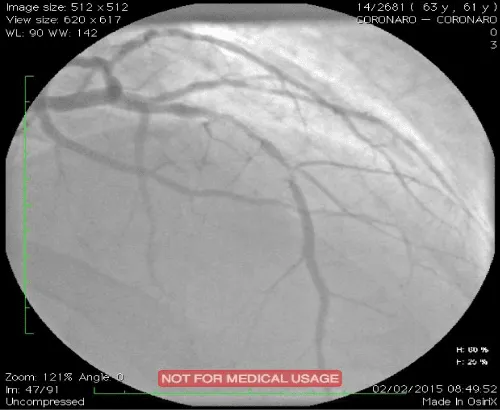

Type B lesions were the most frequent: B1=31.6% and B2=36.8%. Three patients had C-type lesions. Single-truncal affection was predominant (76.3%). Multi-truncular lesions included two-truncular ones (21.1%) and tri-truncular ones (01 patients). The SYNTAX score varied between 2 and 28 with an average value of 8.9. A balloon pre-dilation was carried out in 36.8% of the cases. Direct stenting concerned 63.2% of procedures. Twenty-one bare stents (55.3%) and 17 active stents (44.7%) were implanted. The average number of stents per patient was 1.18. The average diameter of the stents was 3.25 and the average length was 17.4 mm. The results were excellent in 94.7% of cases with a TIMI grade 3 flow and without dissection. The average hospital stay in post-angioplasty was 2.31 days [01-08 days]. Intra-hospital progression was favorable in 35 of our patients (92.1%). Two early deaths during the first 48 hours were recorded. One case of acute stent thrombosis was noted 24 hours after angioplasty. At 2 and 6 months, two cases of angina due to exercise and three cases of dyspnea stage II-III of the NYHA were noted clinically. Electrical abnormalities were mainly related to changes in the ST segment with epicardial ischemia. Nevertheless, a third death occurred following a probable angina attack less than 2 months post ATL. Echocardiography of dobutamine stress during follow-up was positive in 04 patients (12.5%). Control coronary angiography performed in two patients revealed very tight in-stent restenosis (Figure 1). The predictive factors for restenosis were dominated by a deterioration of the segmental kinetics (p=0.009), the diastolic function (p=0.002), the systolic function (p=0.003), a high post angioplasty troponin (p=0.004), the presence of calcifications (p=0.004) and a high SYNTAX score ≥ (p=0.021) (Table 1).

Figure 1: Drug-eluting in-stent restenosis of left anterior descending coronary artery in a patient with a positive stress echocardiography.